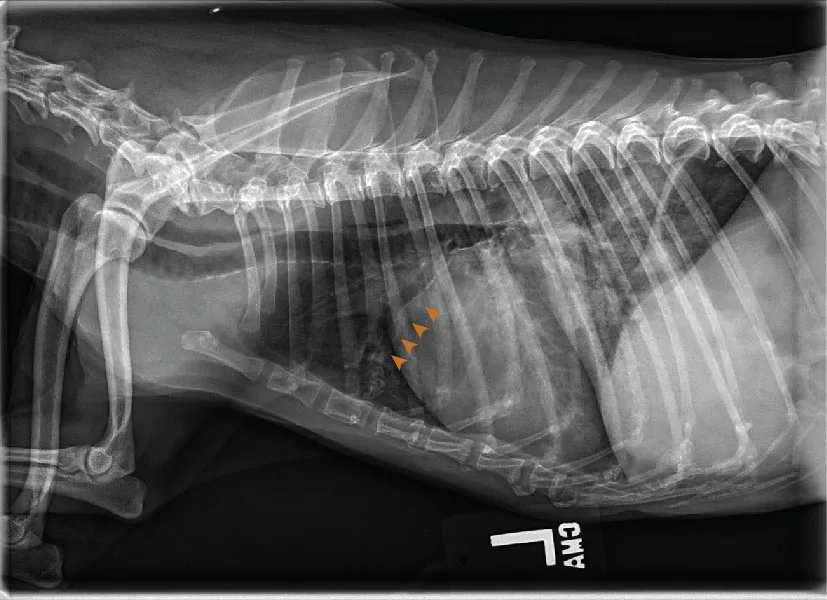

FIGURE 11 Right lateral (left) and VD (right) projections of a crossbreed dog with tricuspid valve dysplasia. The cardiac silhouette has increased width, and the regions of the right atrium and ventricle show roundness. The cardiac apex is displaced to the left secondary to right-sided enlargement (right). The caudal vena cava (arrowheads) is dilated, and there is loss of abdominal serosal detail secondary to increased systemic venous pressures and right-sided CHF, respectively. The pulmonary vasculature is small secondary to pulmonary hypoperfusion (given significant regurgitation across the tricuspid valve and decreased forward blood flow). VHS, VLAS, M-VLAS, and VRHi collected from the right lateral view are 12.3, 2.3, 2.7, and 3.8, respectively. Images courtesy of Bruna Del Nero, DACVIM (Cardiology)